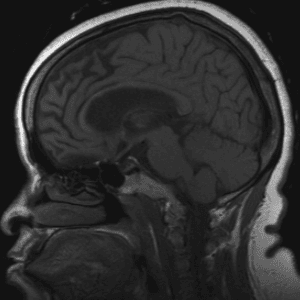

Neurodegenerative Diseases